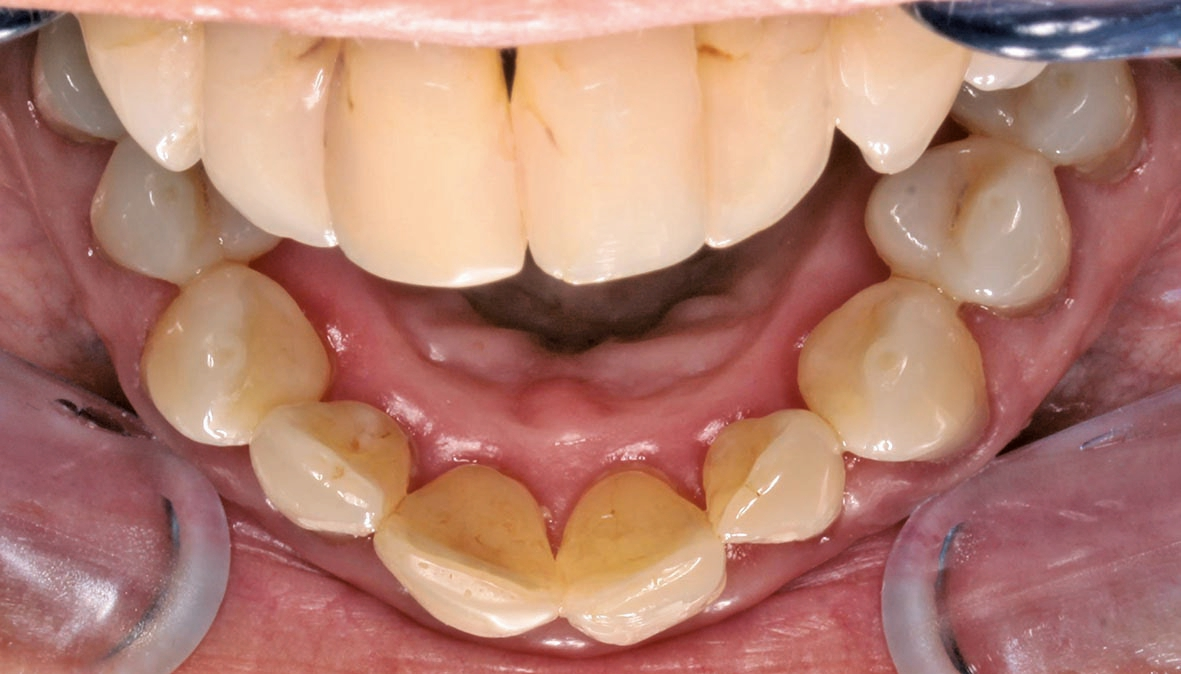

Unsere Patientin stellte sich mit einer starken Parodontitis (Abb. 1a–c) und einer schlechten Mundhygiene in der Praxis von Zahnarzt Andreas Klinkisch (Weidenberg und Bischofsgrün) vor. Am Anfang standen zunächst die Motivation zur besseren Mundhygiene, dann die konkrete Anleitung zum gründlichen Zähneputzen und schließlich die Begleitung der Maßnahmen. Nach diesem Prozess, der fast ein Jahr beanspruchte, stellte sich die 67 Jahre alte Patientin bei mir mit dem großen Wunsch vor, wieder natürliche, ästhetische und etwas hellere Frontzähne mit geschlossenen interdentalen Bereichen zu haben.

Wir sehen uns in derart gelagerten Fällen stets mit mehreren Herausforderungen konfrontiert, vor allem mit diesen: Zum einen müssen die Materialien zuverlässig und robust sein, zum anderen sollen mir die Materialien erlauben, feinste altersspezifische und individuelle Merkmale zu berücksichtigen und „nachzubauen“. Bei dieser Patientin waren die Zähne leicht fluoreszierend, das inzisale Drittel transparent und in der Schneidekante leicht opaleszent. Das Dentin und der Zahnhalsbereich hingegen wirkten stark chromatisch. Auch wollten wir, dass sich das Zahnfleisch bestmöglich an das Material adaptiert. Auch das würde helfen, die schwarzen Dreiecke im Frontbereich zu schließen.